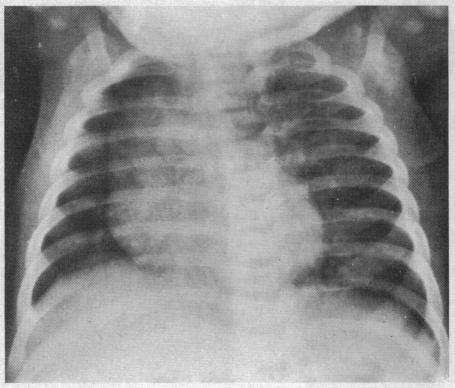

Partial tracheal obstruction due to anomalous origin of the left pulmonary artery.